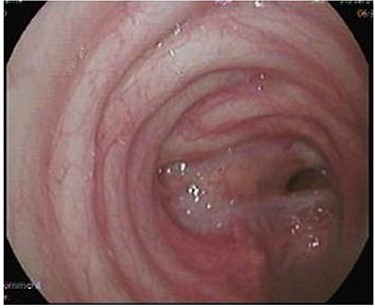

After discharge, the patient presented to the Emergency Room with shortness of breath and tachypnea. Chest X-rays and CT scan were unremarkable; however, he was admitted with type 2 respiratory failure and placed on noninvasive ventilation. Due to persistent tachypnea, the patient’s initial CT scans were reassessed with reconstruction and showed a complete transection of the trachea that was overlooked initially (Fig. 2). Flexible bronchoscopy revealed a significant post-traumatic tracheal stenosis (Fig. 3). It was tight stenosis (2 cm length on the CT reconstruction) and just above the carina. The patient was taken to the OT, with the ECMO team on standby. During rigid bronchoscopy, the patient became more hypoxic, and VV-ECMO was instituted. The stenosis was dilated with a small (#6) endotracheal tube (ETT) placed across the stenosis. He subsequently returned to the OT for further dilation and placement of a # 7.5 ETT. After 9 days, bronchoscopy revealed no gross residual stenosis and therefore the patient was successfully extubated. The patient was removed from ECMO support on the following day. After several days, the patient developed tachypnea, tachycardia and a respiratory acidosis. He was reintubated and shifted to the OT again (with ECMO standby) for redilation of restenosis with a #8 ETT in place. A covered tracheal stent was placed intraoperatively via rigid bronchoscopy (Fig. 4 A–C). Later on, the patient was extubated and eventually discharged home in stable condition.

(A) Rigid bronchoscopy show 4 mm stenosis of the distal trachea, (B) intra-tracheal showing the stent following dilatation and placement of stent, (C) plain X-ray showing stent in place, feeding tube and endotracheal tube.